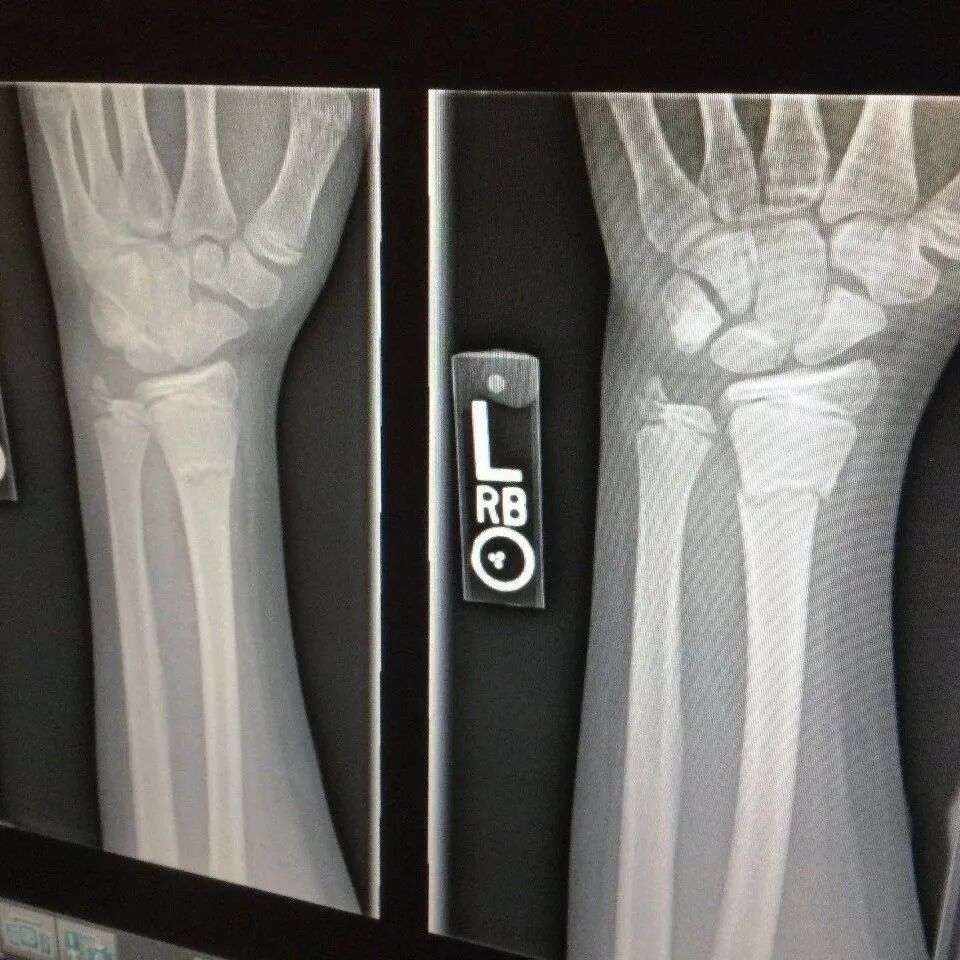

X 光

# X光检查 #

# 胸透和胸片/DR检查是什么 #

俗称拍片,最常见的影像检查,X射线具有穿透性,但人体组织间有密度和厚度的差异,当X射线透过人体不同组织时,被吸收的程度不同,经过显像处理后即可得到不同的影像。

胸透和胸片DR作用

胸透和胸片主要用于检查诊断肺部疾病、心脏的大小、肋骨、胸膜、胸壁纵隔、支气管。为减少X线的损害,患者做检查不宜过多。

胸片DR和胸透还是有很大的区别的,当然它们都是检查胸部,也就是看肺这一块的。但是它们的区别还是比较大的,首先第一点它的辐射剂量有很大的差别,胸片DR,它的辐射剂量是非常的小,而胸透相对来说就要大一些了,主要是跟它辐射的时间有关系。

做胸片DR检查的话,它辐射的时间是非常短的,一般也就是零点零几秒的时间,非常的短,而胸透检查它这个辐射时间相对来说就要长一些了,一般是需要十秒钟的时间。当然如果发现有可疑的病灶,可能需要看的时间要更长一些了。正因为是这样,所以现在很多医院已经基本上取消了胸透检查了,都是用胸片来进行替代。

胸片的话一般是可以照出一张片子来,而胸透只是医生通过目视,通过眼睛来看,看完之后得出一个纸质报告,是没有这种片子的。

做胸片/DR注意事项

1 拍DR辐射会很大吧?

随着X光仪器不断改进,其放射剂量越来越小,加上胸透检查一般也在十几秒以内,对人体的危害非常微小,基本可忽略。

X-ray

2 检查时取下身上的金属物品

因为金属会影响胸透的影像,所以大家在去做胸透时,不要穿有金属装饰或者金属扣子的衣服,另外,女性文胸上的钢圈有时也需要注意,如果医生要求脱掉内衣,女性们应该有自我保护意识,去洗手间脱下文胸再穿上外衣进行胸透,要知道衣服是不会影响胸透的。

3 怀孕能做胸透吗?

怀孕是不可以做胸透的,因为胸透使用的X射线会辐射人体,而这种辐射是有致胎儿畸形的可能的,尤其是怀孕的女性要注意,在孕期不要做胸透。

不过如果不小心做了胸透的准妈妈也不要太过担心,因为胸透检查的辐射剂量是有限制的,而且胸透也不会照射腹部,所以胎儿不一定会受到影响,这时候准妈妈们需要去医院检查,以确定胎儿没有受到辐射的影响。

最常用X光片、CT大致了解选X光片,细致分析选CT肺的检查一般不选核磁

最常用X光片

诊断不明确,可用CT

骨骼、四肢